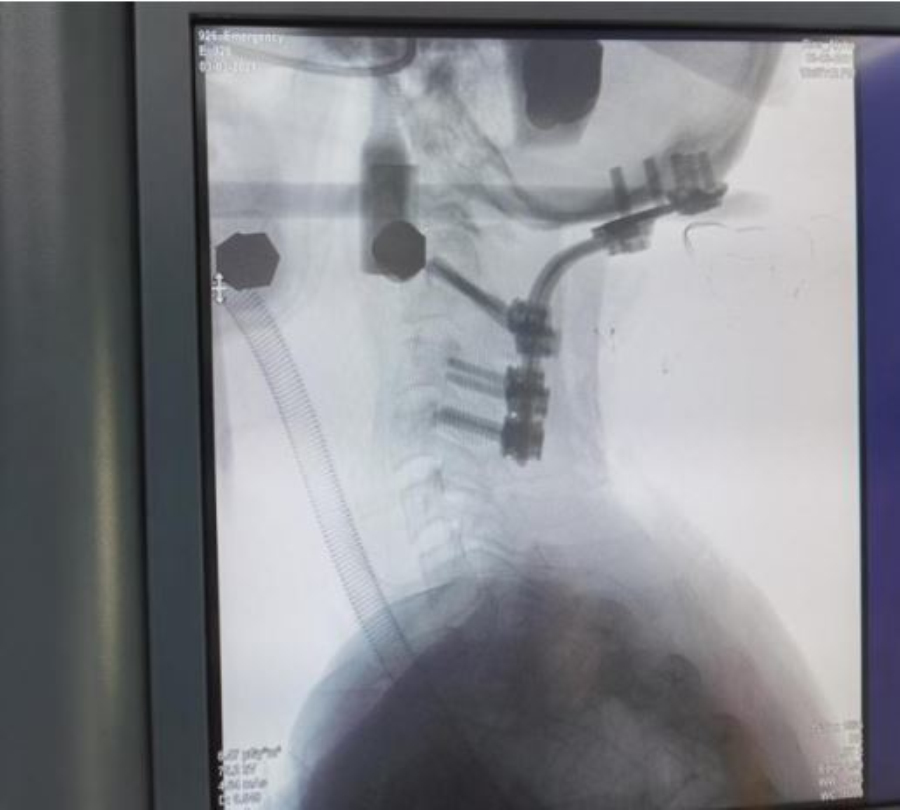

3月3日清晨,手术麻醉科按计划迎来了这位患者,麻醉科团队为患者进行麻醉前的精心准备,并备好了各种抢救药品,完善抢救预案。在可视化技术的辅助下,静脉给药,面罩给氧,平稳、准确、迅速地完成气管插管,为患者顺利地完成了全身麻醉。在颈椎外科、微创脊柱外科及麻醉科多名专家的团结协作和默契配合下,手术历时4小时顺利完成。术后患者自觉僵硬麻木缓解,肌力进步。目前患者生命体征平稳,正在接受进一步恢复治疗中。

术毕颈椎X光片